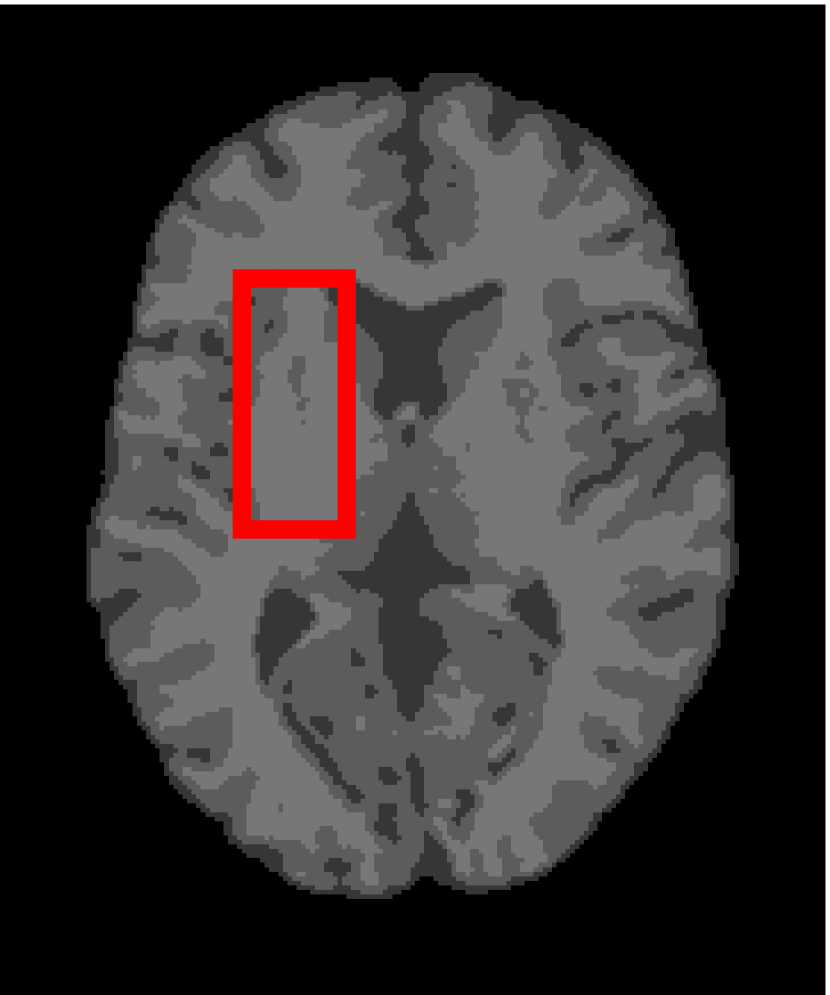

Next, we representatively segment five medical images from BrianWeb. They are represented as five slices in the axial plane with a sequence of 70, 80, 90, 100 and 110, which are generated by T1 modality with slice thickness of 1mm resolution, 9% noise and 20% intensity non-uniformity. Here, we set c=4𝑐4c=4 for all cases. The comparison between WRFCM and its peers are shown in Fig. 9 and Table II. The best values are in bold.

Figure 9: Segmentation results on five medical images. The parameter: ϕ=5.35italic-ϕ5.35\phi=5.35. From top to bottom: noisy images, ground truth, and results of FCM_S1, FCM_S2, FLICM, KWFLICM, FRFCM, WFCM, DSFCM_N, and WRFCM.

By a view of the marked red square in Fig. 9, we find that FCM_S1, FCM_S2, FLICM, KWFLICM and DSFCM_N are vulnerable to noise and intensity non-uniformity. They give rise to the change of topological shapes to some extent. Unlike them, FRFCM and WFCM achieve sufficient noise removal. However, they produce overly smooth contours. Compared with its seven peers, WRFCM can not only suppress noise adequately but also acquire accurate contours. Moreover, it yields the visual result closer to ground truth than its peers. As Table II shows, WRFCM obtains optimal SA, SDS and MCC results for all five medical images. As a conclusion, it outperforms its peers visually and quantitatively.